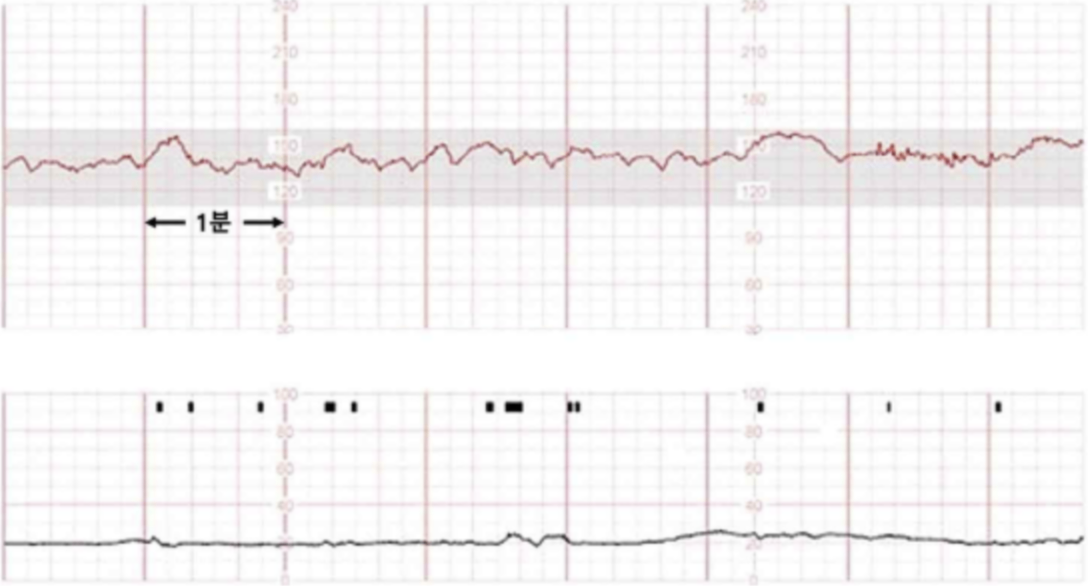

임신 22주인 26세 미분만부가 2일 전부터 왼쪽 옆구리가 아파서 병원에 왔다. 혈압 110/70 mmHg, 맥박 90회/분, 호흡 20회/분, 체온 39.0°C이다. 복부에 압통이나 반동압통은 없고, 왼쪽 갈비 척추각에 압통이 있다. 골반검사에서 자궁경부는 닫혀있다. 자궁 수축감시검사 결과이다. 검사 결과는 다음과 같다. 처치는?

Fetal CTG: FHR nl, no uterine contraction

• 리토드린 정맥주사: Fetal CTG 및 골반검사 결과 조기진통이 의심되지 않으므로 자궁수축억제제를 사용할 필요는 없다.